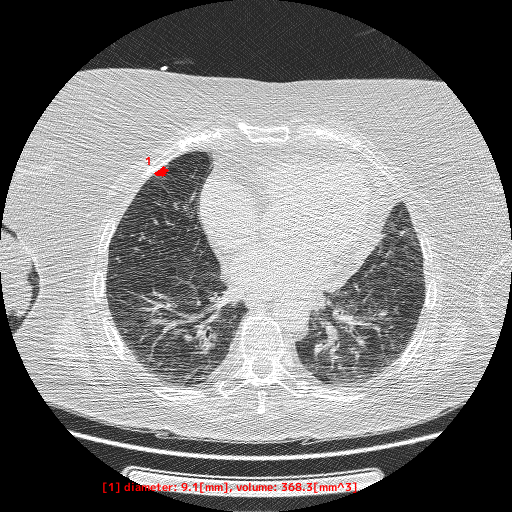

本製品は、胸部CT画像から肺野領域の組織について、使用者が設定した基準値に基づくCT値から「関心領域」を抽出し、その体積と最大径を自動計測します。計測した最大径が閾値以上となった場合には、画像上に色付けして表示します。この抽出・計測・表示機能は、医師が胸部CT画像を対象に読影診断を行う際に併用することで、肺野周辺組織とCT値が異なる肺結節等の視認性向上に寄与することが期待されます

【EIRL Chest CTによる表示例】

② 低線量CT

- 低線量CTについて

- 通常のCTに比べ、被検査者に与える被ばく量を軽減することが可能です。一方、撮影される画像は、通常のCTに比べて質が低下する傾向にあり、読影診断の難易度が高まると言われています。